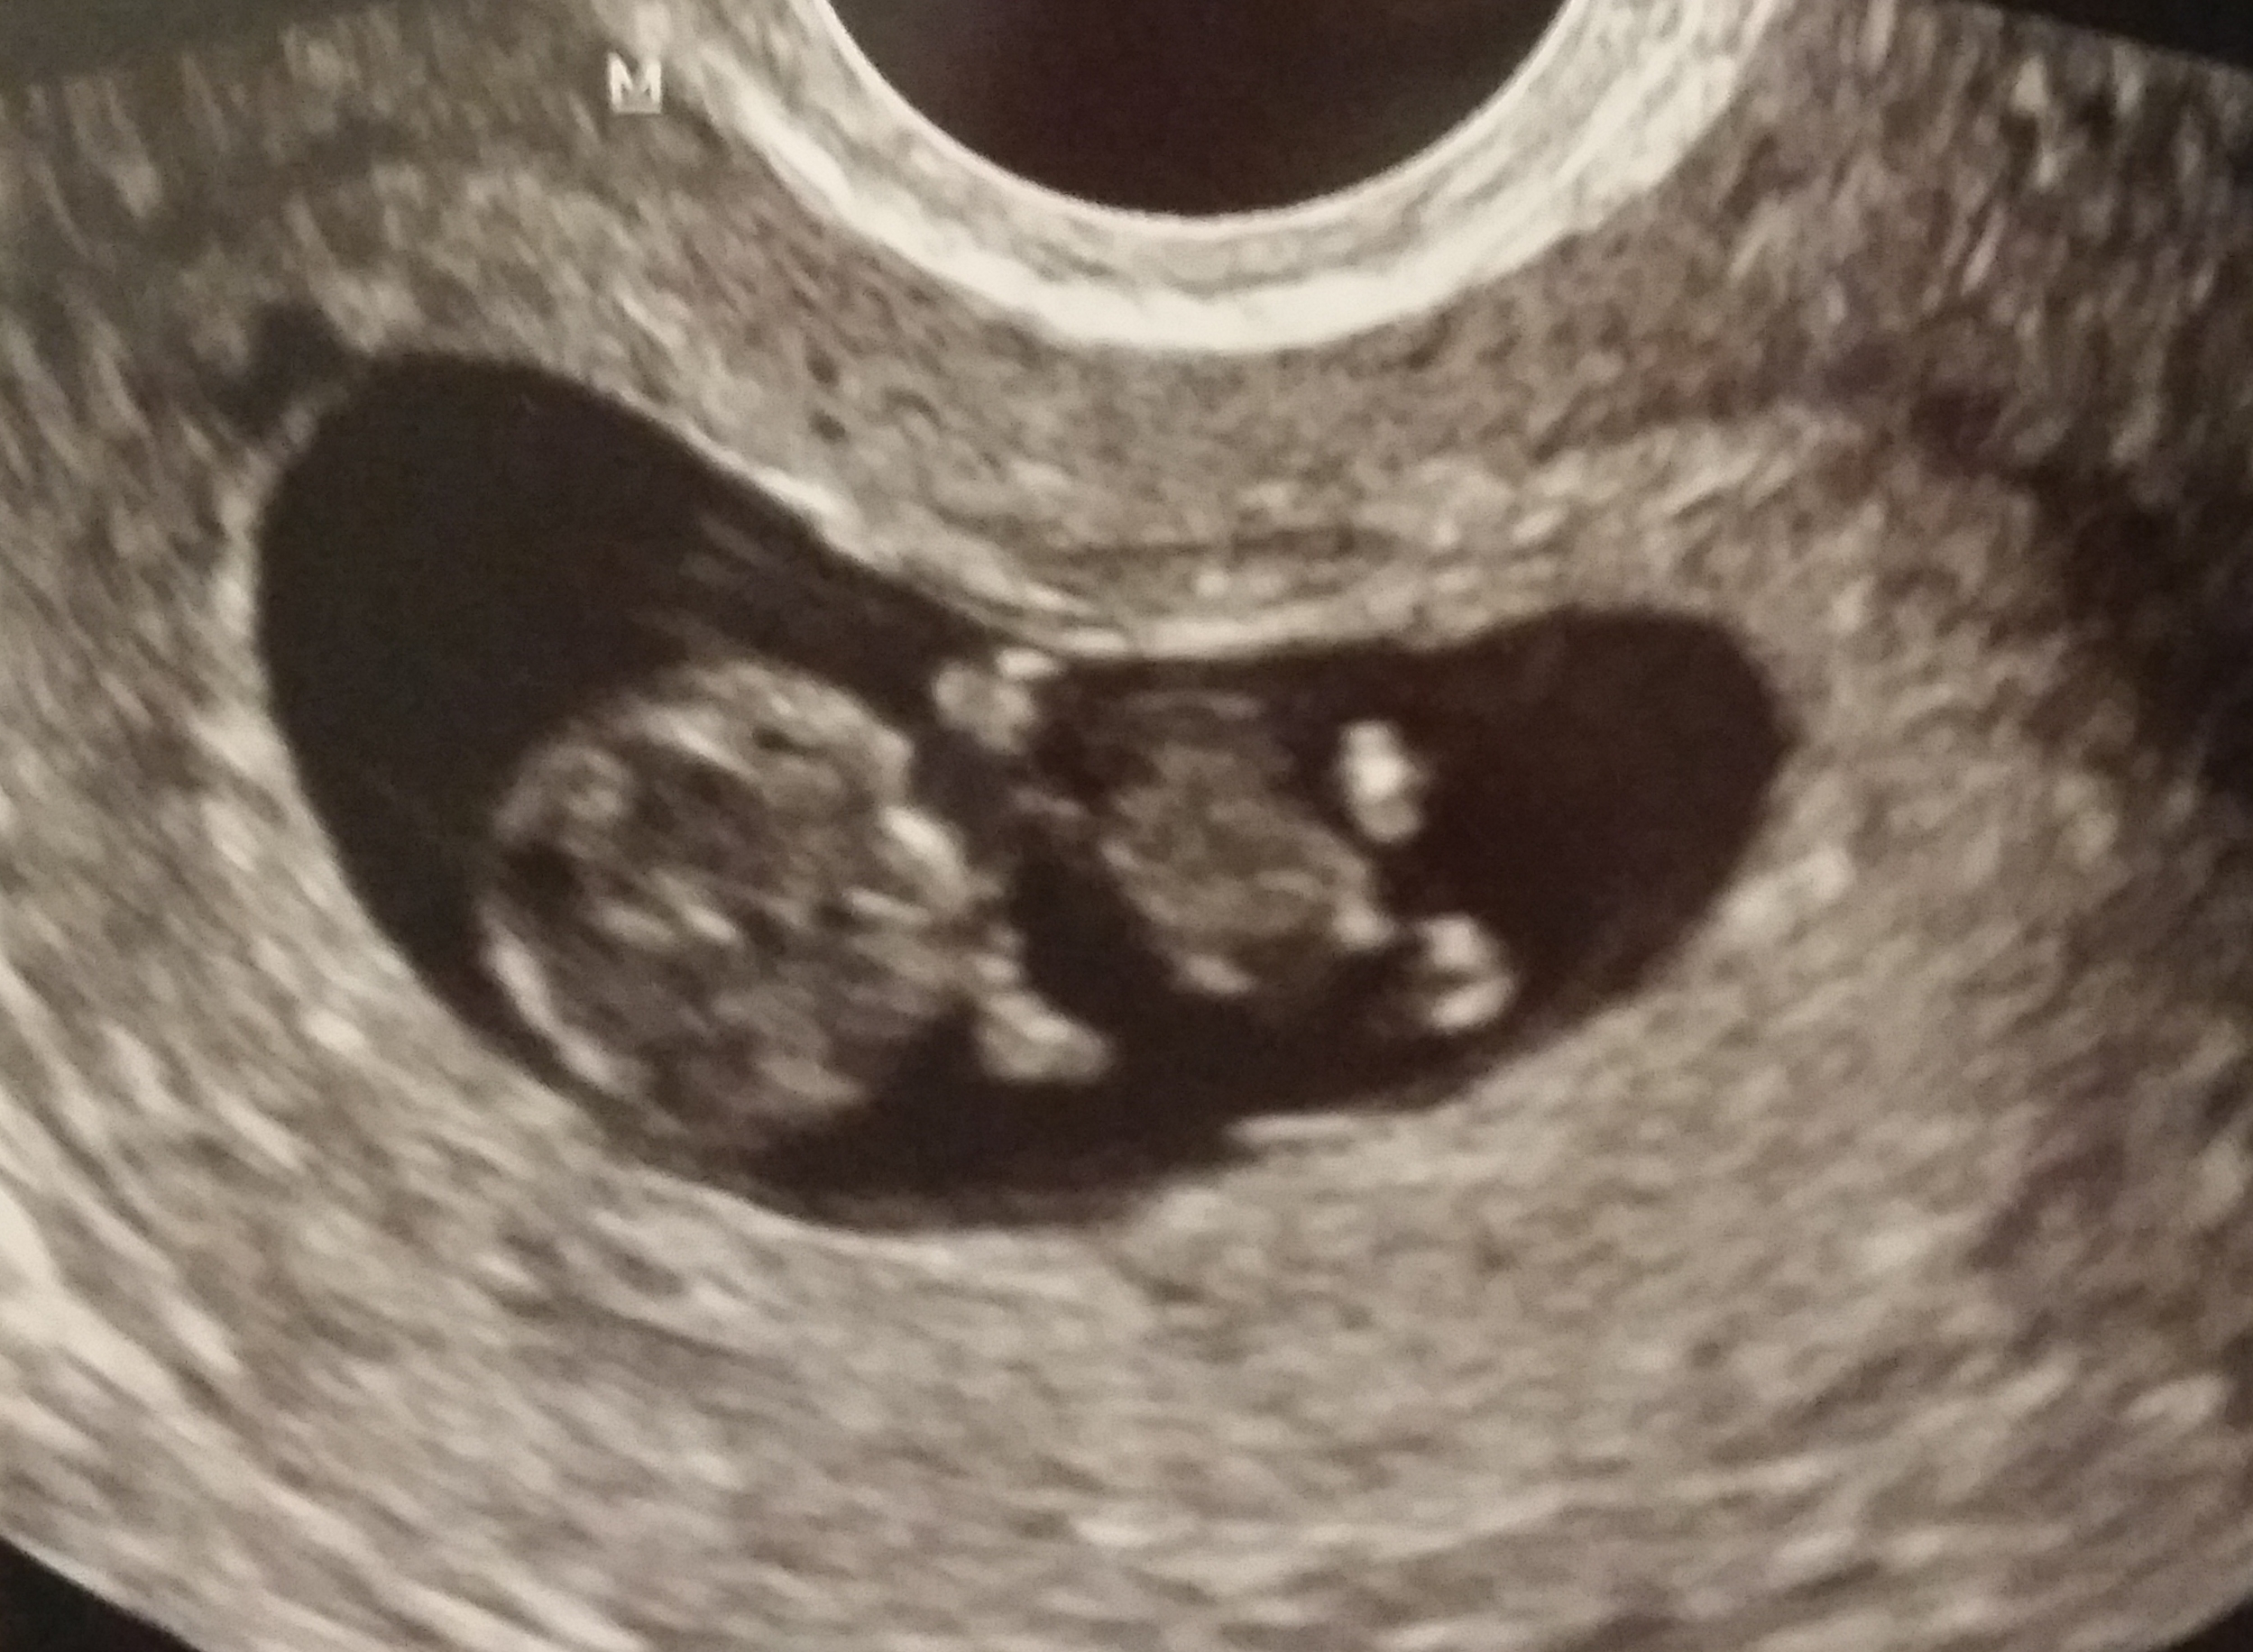

My baby at 11 weeks! Can't wait to have my 12 week scan on Tuesday

So cute! it is a perfect tiny baby!! How did you manage to get scans at 11 and 12 weeks? So jealous!! I can't wait to see our little passenger again next week. Thanks for sharing. Xo